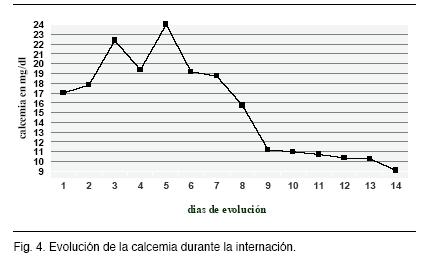

A las 72 hs., coincidiendo con el aumento de la cifra de calcemia, instaló depresión de conciencia, en apirexia y sin elementos de hipertensión endocraneana ni focalidad neurológica, presentando al examen un Glasgow 12 (Figuras 3 y 4). Se plantea su etiología metabólica (hipercalcemia, deshidratación) y se descartan causas infecciosas o estructurales (tomografía de cráneo normal y punción lumbar con citoquímico normal y cultivo estéril).

En el caso clínico analizado observamos que el nivel de calcemia se correlaciona con el deterioro del nivel de conciencia. Coincidiendo con la literatura revisada.